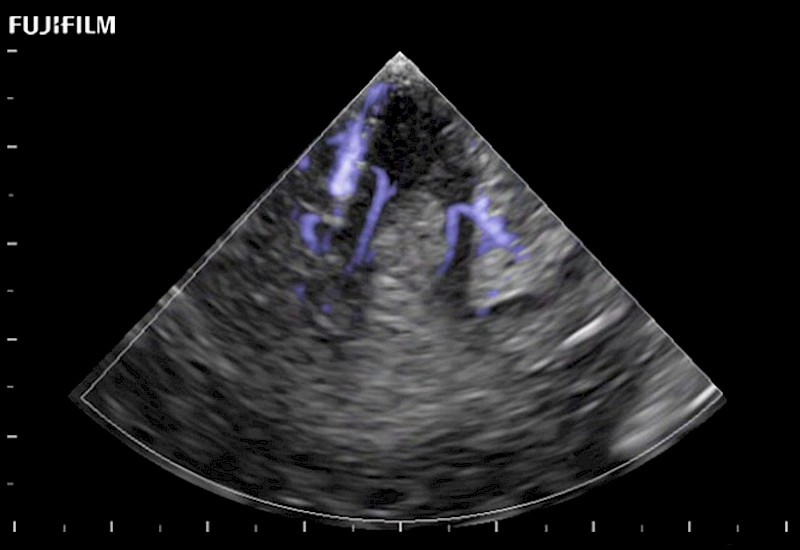

Exclusive 10mm side‐fire linear array transducer with 2.87mm diameter is ideal for real‐time visualization through and behind structures and instant, scalable definition of anatomy and vascularity including the ability to delineate and define tumor margins.

Main Specifications: